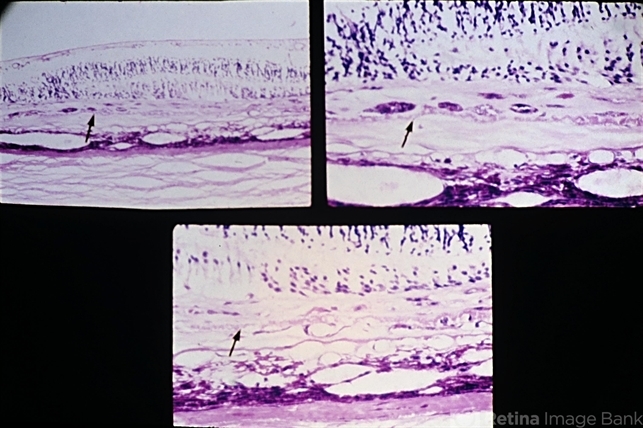

- macular degeneration, disciform scar, Bruch's membrane, retinal pigment epithelium, choroidal neovascular tissue

- Senile macular degeneration. A disciform scar is shown in a typical two component configuration. Arrows indicate the thickened and detached inner aspect of Bruch's membrane. There is one component of the disciform lesion that is located between the retina and the detached inner aspect of Bruch's membrane. RPE hyperplasia is evident in this component. The second component is located between the two layers of Bruch's membrane, and this component has choroidal neovascular tissue in the lower view.